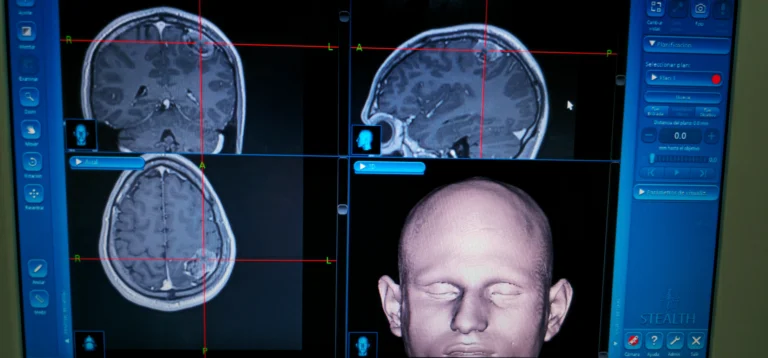

Specialist in the diagnosis and surgical management of conditions of the nervous system, with expertise in minimally invasive spine surgery, skull base procedures, neuro-oncology, and complex cranial and spinal pathologies.

- ✔ General and Advanced Neurosurgery

- ✔ Skull Base Surgery

- ✔ Endoscopic Brain Surgery

- ✔ Minimally Invasive Spine Surgery

- ✔ Neuro-oncology

- ✔️ General and advanced neurosurgery

- ✔️ Skull base surgery

- ✔️ Endoscopic brain surgery

- ✔️ Minimally invasive spine surgery

- ✔️ Brain and spine tumor surgery

- ✔️ Neuro-oncology